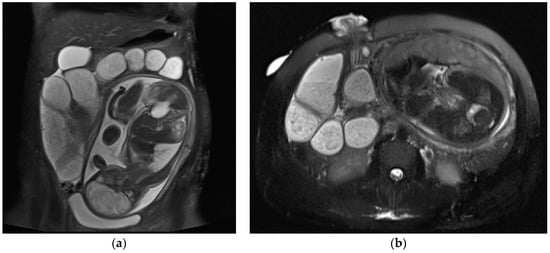

Most ovarian masses diagnosed in pregnancy are benign and are spontaneously resolved (Figure 9). Surgical management is warranted when masses are suspicious for malignancy, at risk for torsion or clinically symptomatic [3].

Figure 9.

Left adnexal torsion in 28-year-old patient at 35 weeks of gestation. Axial (a) and coronal (b) T2-weighted images show left cystic formation of about 8 cm (arrow) that has undergone torsion, compressed between the gravid uterus and the abdominal wall.